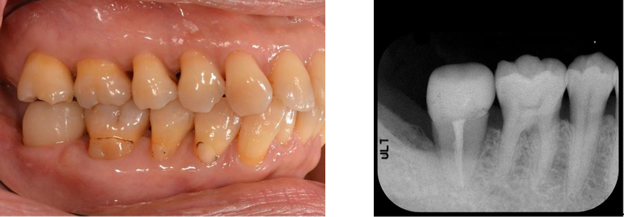

4番のフェルール、インプラント前処置として角化歯肉獲得

オペ GBR ファイナルセット